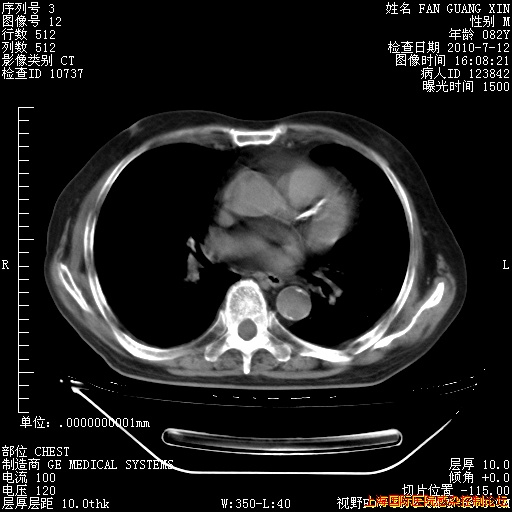

补发6月12日肺部CT肺窗

6月12日肺窗

6月12日纵膈窗

今天复查CT

今天CT

整整相隔30天的肺部CT好像有所好转啊。甲强龙减量第3天,需要观察体温。

海管,自昨日你和我通完话后,不知您岳父消化道症状有无缓解?体温怎样?阅读7.12日胸部ct,个人认为目前激素治疗是有效的,甲强龙减量是适宜的。因在抗痨治疗,需密切观察肝功、肾功能和血常规。不过,老年、长期住院和大量使用激素,很担心菌群失调发生